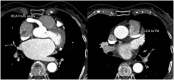

Case summary: We present a case of a 76-year-old patient with first presentation of ALCAPA. The coronary anomaly was first diagnosed during elective coronary angiography. The case was discussed at the Heart Team meeting and as the patient was asymptomatic, had good coronary collateral circulation, a medical treatment strategy was chosen and the patient was discharged in a good physical condition. During 3 years of follow-up, the patient has experienced no cardiovascular complications.

Discussion: We hereby also discuss briefly the clinical presentation, epidemiology, diagnostics and treatment options for adults with newly diagnosed ALCAPA and discuss the need for a new clinical classification. Only a few cases have been published of septuagenarians or octogenarians with first presentation of ALCAPA. To our knowledge, the patient presented in our case was one of the least symptomatic patients during her eight decades of life.